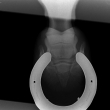

Čip ve spěnkovém kloubu na pánevní končetině